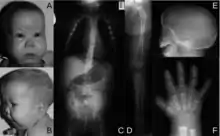

The ability of the Kozak sequence to optimize translation can result in novel initiation codons in the typically untranslated region of the 5′ (5′ UTR) end of the mRNA transcript. A G to A mutation was described by Bohlen et al. (2017) in a Kozak-like region in the SOX9 gene that created a new translation initiation codon in an out-of-frame open reading frame. The correct initiation codon was located in a region that did not match the Kozak consensus sequence as closely as the surrounding sequence of the new, upstream initiation site did, which resulted in reduced translation efficiency of functional SOX9 protein. The patient in whom this mutation was detected had developed acampomelic campomelic dysplasia, a developmental disorder that causes skeletal, reproductive and airway issues due to insufficient SOX9 expression.[32]